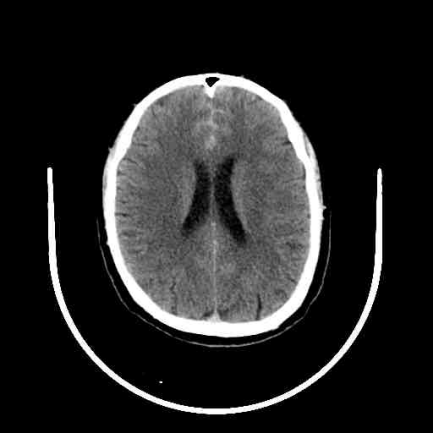

提到脑动脉瘤,很多人以为做完开颅夹闭或介入栓塞手术就万事大吉。但据临床研究:两类手术均存在复发可能!动脉瘤复发率与动脉瘤大小、位置、形态、性质、瘤颈情况、治疗方式、术后即刻结果、抗血小板使用情况等因素相关。因此,定期复查对评估手术效果、术后复发风险及是否需及时干预等至关重要。 真实案例:曾某,54岁,因颅内动脉瘤破裂开颅动脉瘤夹闭术,术后第 3 年突然头痛难忍,复查发现动脉瘤复发并出血,再次行开颅手术挽救了生命。幸亏及时干预才避免悲剧,但不是每个患者都那么幸运! 第一次术前头颅CT 第二次术前头颅CT 划重点:术后定期复查不是“选择题”,而是保命必答题! 为什么要复查? 三大核心目标揭秘 1.评估手术效果:确认动脉瘤愈合情况,是否存在残留或复发。 2.监测并发症:如是否存在脑积水、脑血管狭窄、脑梗死等。 3.调整治疗方案:根据复查结果决定是否需要调整用药或进一步干预。 三大复查项目 1.CT血管成像(CTA):具有快速、经济、无创的特点,可作为颅内动脉瘤术后的常规影像学随访手段,需要静脉注射造影剂后行CT检查,可以较好地显示动脉瘤术后的血管结构,了解动脉瘤夹或栓塞材料的位置及周围血管情况,同时可以显示有无脑积水等情况。 2.磁共振血管成像(MRA):是一种无创检查,不需要注射造影剂,对人体无辐射,能较好地显示脑血管的大致形态和脑动脉瘤术后情况。 3.脑血管造影(DSA):是一种微创检查,为脑动脉瘤检查的“金标准”,它能清晰显示动脉瘤夹闭或栓塞后的情况,准确判断动脉瘤有无残留、复发以及血管的通畅程度。 动脉瘤治疗后复查周期怎么定? 1.对于复发低风险患者:推荐术后1月复查头颅CT,半年和一年连续两次头颅CTA或DSA(至少一次DSA),如两次结果均为治愈,可3-5年复查一次。 2.对于复发风险高的患者:术后3个月、6个月和1年分别进行一次CTA或DSA(至少一次DSA),部分复发风险高的患者甚至在出院前需复查一次CTA或DSA。 3.对于术后动脉瘤夹闭或栓塞效果满意的患者:建议在术后半年或1年完成一次DSA。若复查显示动脉瘤完全闭塞且无显影,后续可延长复查间隔至每3-5年一次。 (以上复查时间仅供参考,具体时间需专科医师个体化决定,详情请咨询神经外科:0830-5216264 ,地址:门诊综合楼二楼204室) 脑动脉瘤复发了怎么办?这些救命知识要知道 如果复查发现动脉瘤复发,千万别慌!虽然复发动脉瘤发生瘤体增大、破裂出血的风险更高,但目前有多种成熟治疗手段。以下是复发动脉瘤处理措施包括但不限于: 1.减少抗血小板药物的使用; 2.再次开颅夹闭术或介入栓塞术或开颅夹闭+介入栓塞复合手术; 3.搭桥或载瘤动脉闭塞孤立动脉瘤术。 随着手术技术及手术材料的发展,动脉瘤复发率正逐年减低,随访周期及方法也在不断地变化,正确、规律的随访仍然是降低动脉瘤致死和致残率的有效方式。 最后敲黑板!三条“生存法则”请牢记 1.术后第一年是复发高峰,务必严格按医嘱复查。 2.出现突发头痛、呕吐、意识模糊等症状,立即就医! 3.选择同时具备开颅 + 介入技术的医院,为二次治疗留足空间 转发提醒:脑动脉瘤被称为“颅内不定时炸弹”,转发本文给身边有需要的人,一次提醒可能挽救一条生命!